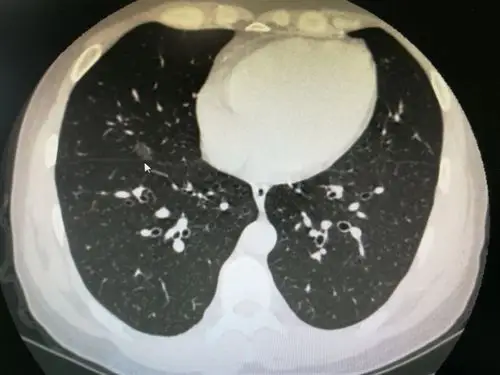

肺结节到底是良性,还是恶性,如何辨别?这些特征需警惕

图文教你看懂恶性肺结节的ct表现

实性肺结节的良恶性ct征象解析